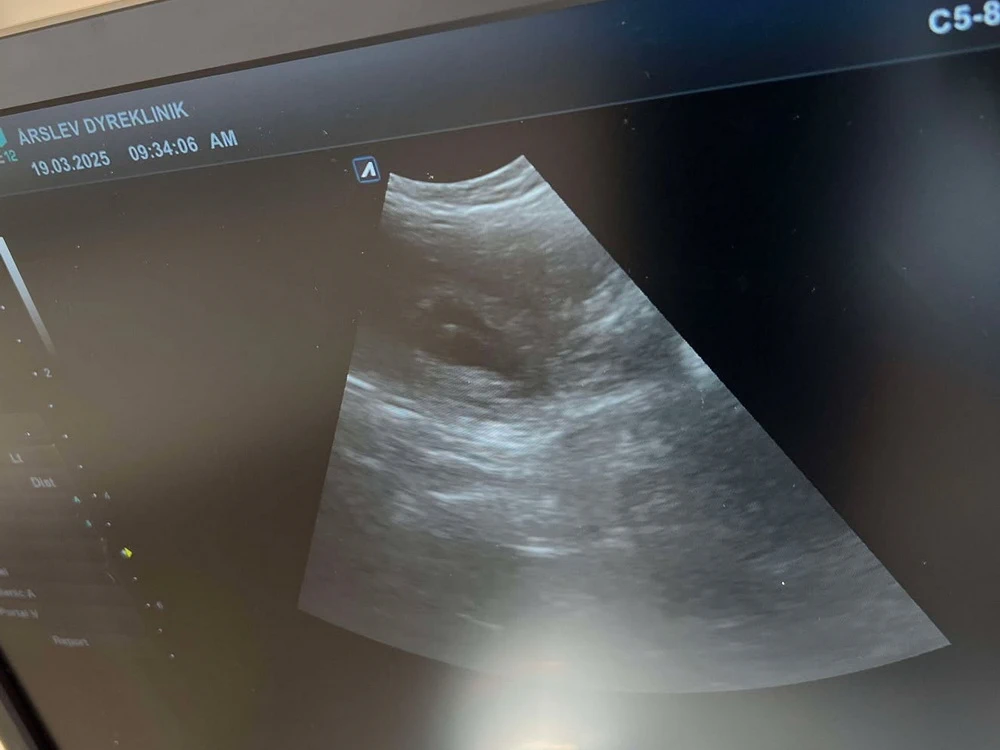

I dag fik vi et lille kik ind i Zoes mave. Og vi så de fineste små bobler på scanningen. Vi forventer et middelstort kuld og der er stadig muligt at blive skrevet op til hvalp.